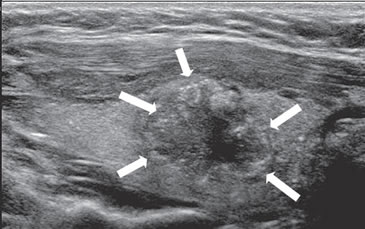

El margen irregular, mal definido, lobulado o determinado por un halo grueso hipoecogénico es un signo de malignidad, pero tiene una sensibilidad muy variable (10%-97%), y la mayor variabilidad inter observador de todos los signos ecográficos, especialmente cuando los estudios son retrospectivos, y los equipos son de diferente calidad. En todo caso, un margen mal definido e irregular, de aspecto infiltrativo, indica con alta probabilidad que el nódulo es maligno (Figura 7 a y b).

Figura 15. a) Cáncer papilar sólido de bordes lobulados (flechas) que muestra una gruesa calcificación central (flecha abierta) y múltiples

microcalcificaciones; b) Adenopatía cervical del grupo IV del mismo paciente (figura 15 a), hiperecogénica, con elementos quísticos (flecha

blanca) y microcalcificaciones agrupadas (flechas negras), típica de cáncer papilar; c) Adenopatías de grupo IV de un cáncer papilar, de

forma redondeada, hiperecogénicas, con pérdida del hilio, una anterior a la arteria carótida común (flecha) y otra lateral a la vena yugular

interna (flecha abierta); d) Corte sagital de la adenopatía lateral de la imagen 15 c), que en “doppler color” muestra vascularización patológica

y pérdida del hilio.